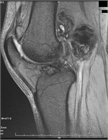

1. 関節水腫の原因となる疾患を、貯留した関節液の性状から、1)非炎症性2)炎症性3)化膿性4)血性の4グループから原因疾患を分類して考える(推奨度2)

1. その原因として、変性疾患、リウマチ性疾患、化膿性疾患、腫瘍性疾患、それに外傷などがある(推奨度2)